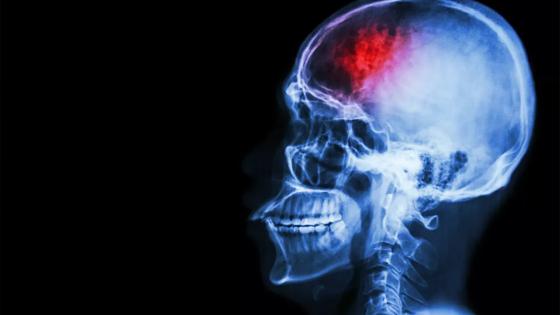

Инсульт – это острое нарушение кровообращения в головном мозге и одна из основных причин инвалидности и смертности во всем мире. Врач рассказала об основных его признаках.

Часто первые симптомы инсульта замечают окружающие без медобразования. Важно распознать признаки инсульта в первые минуты и вызвать скорую. Спасти человека от инвалидности можно в первые 4,5 часа после начала приступа.